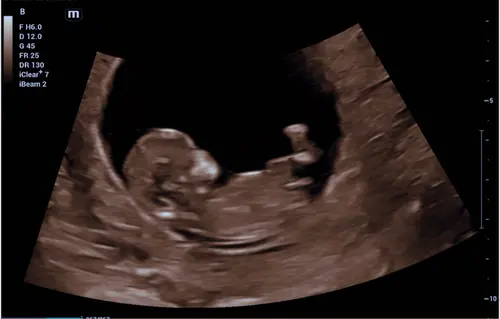

Iemand die hier iets in ziet? Deze echo is van precies 12 weken! 2 maart uitgerekend 🩵🩷

Poeh lastig! Ik zou zeggen jongetje als je naar de ruggengraat kijkt?

Ja dat was ook mijn ingeving inderdaad en ook mijn gevoel al vanaf het begin dus ben benieuwd! Die van jou denk ik een meisje?

Ik zie 2 streepjes , meisje 🩷